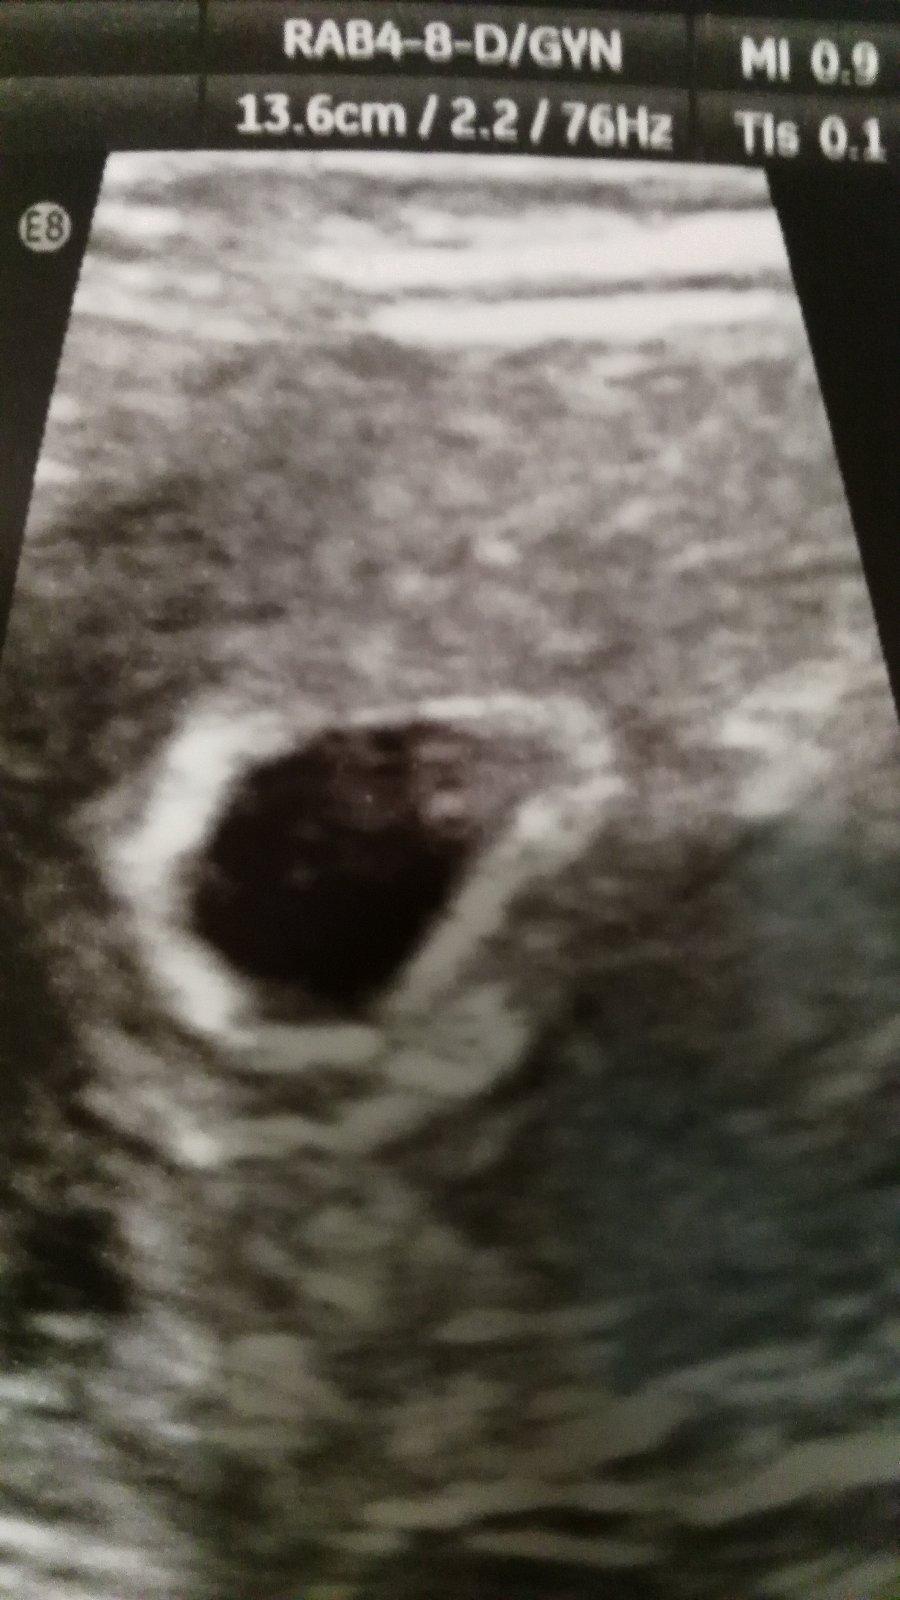

Těhotenský test. Dávám fotku. Co myslíte?

Tak nevim ... ☹ Dávám fotku, skuste posoudit...